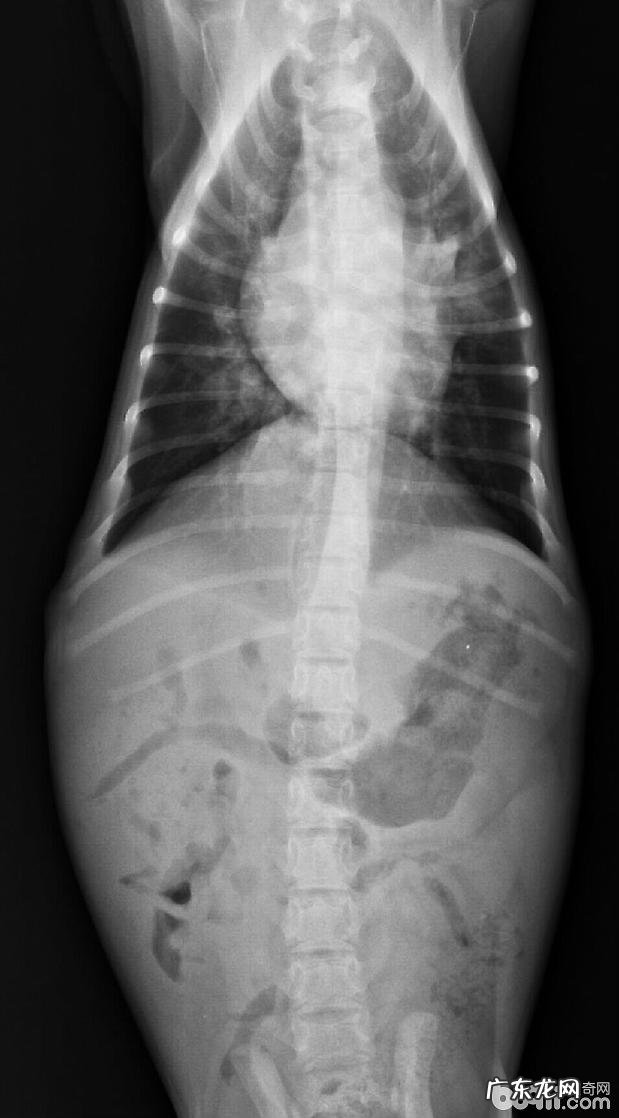

休重:3.5kg , 人体体温:40.0℃ , 心跳:150/min , 吸气:60/min , 身型身体瘦 。精神面貌不佳 , 鼻尖干躁 , 鼻腔有浓鼻涕(如图所示) , 诱咳呈阳性 , CDV(+) , CPV(-) , X光查验肺纹理增大增粗(如图所示) , 粪检(球虫 , 如图所示) , 血常规检查及电解质溶液基本参数见下表

X-光影象显示信息肺炎